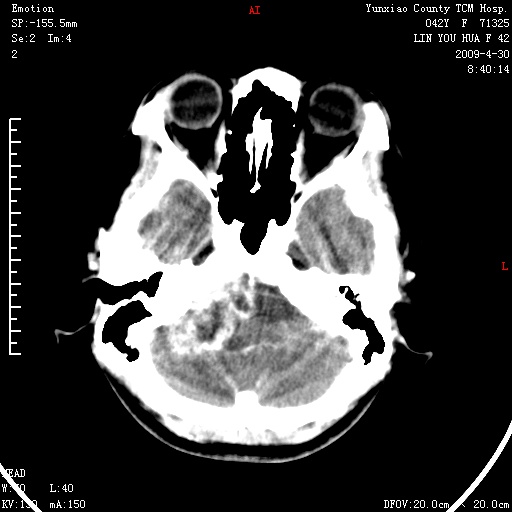

右侧桥小脑角区肿瘤,高密度囊变有显著强化,骨窗见内听道显著扩大,考虑听神经瘤可能性大

1)右侧听神经瘤。2)阻塞性脑积水。

内听道扩大,支持考虑听神经瘤可能性大。